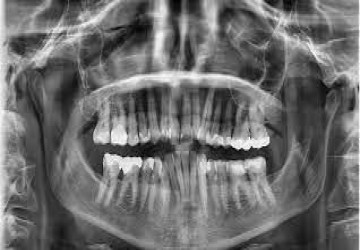

OPG مخفف کلمه Ortho Pantomo Gram می باشد و یکی از پر کاربردترین عکس ها در شاخه دندانپزشکی...